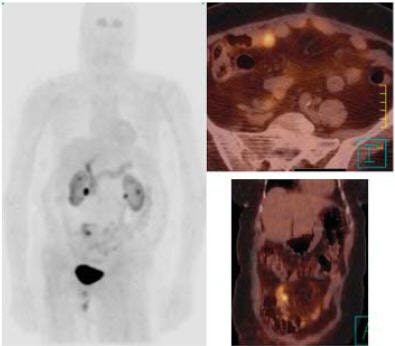

![]() |

Same patient. Above, CT scan 12 weeks after the start of the radionuclide treatment. Below, CT scan done six weeks after completed therapy of 90Y DOTA TATE. RECIST = disease stability. Serum CgA increased. Patient was clinically well at six-month follow-up. Images courtesy of Dr. Jaroslaw Cwikla.